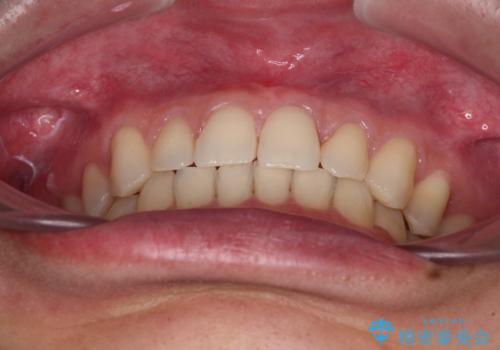

- 歯のデコボコと歯の隙間を気にして来院された患者様です。

隙間の原因は、埋伏や前後に重なってしまっている上顎小臼歯と、下の前歯が見えなくなるくらいのディープバイトで、それらを改善する必要がありました。

顕著なディープバイトのため、頻繁に装置が脱離することがあり、治療期間が想定よりも長くかかることがありますが、当初の予定期間で無事に治療を終えることができました。